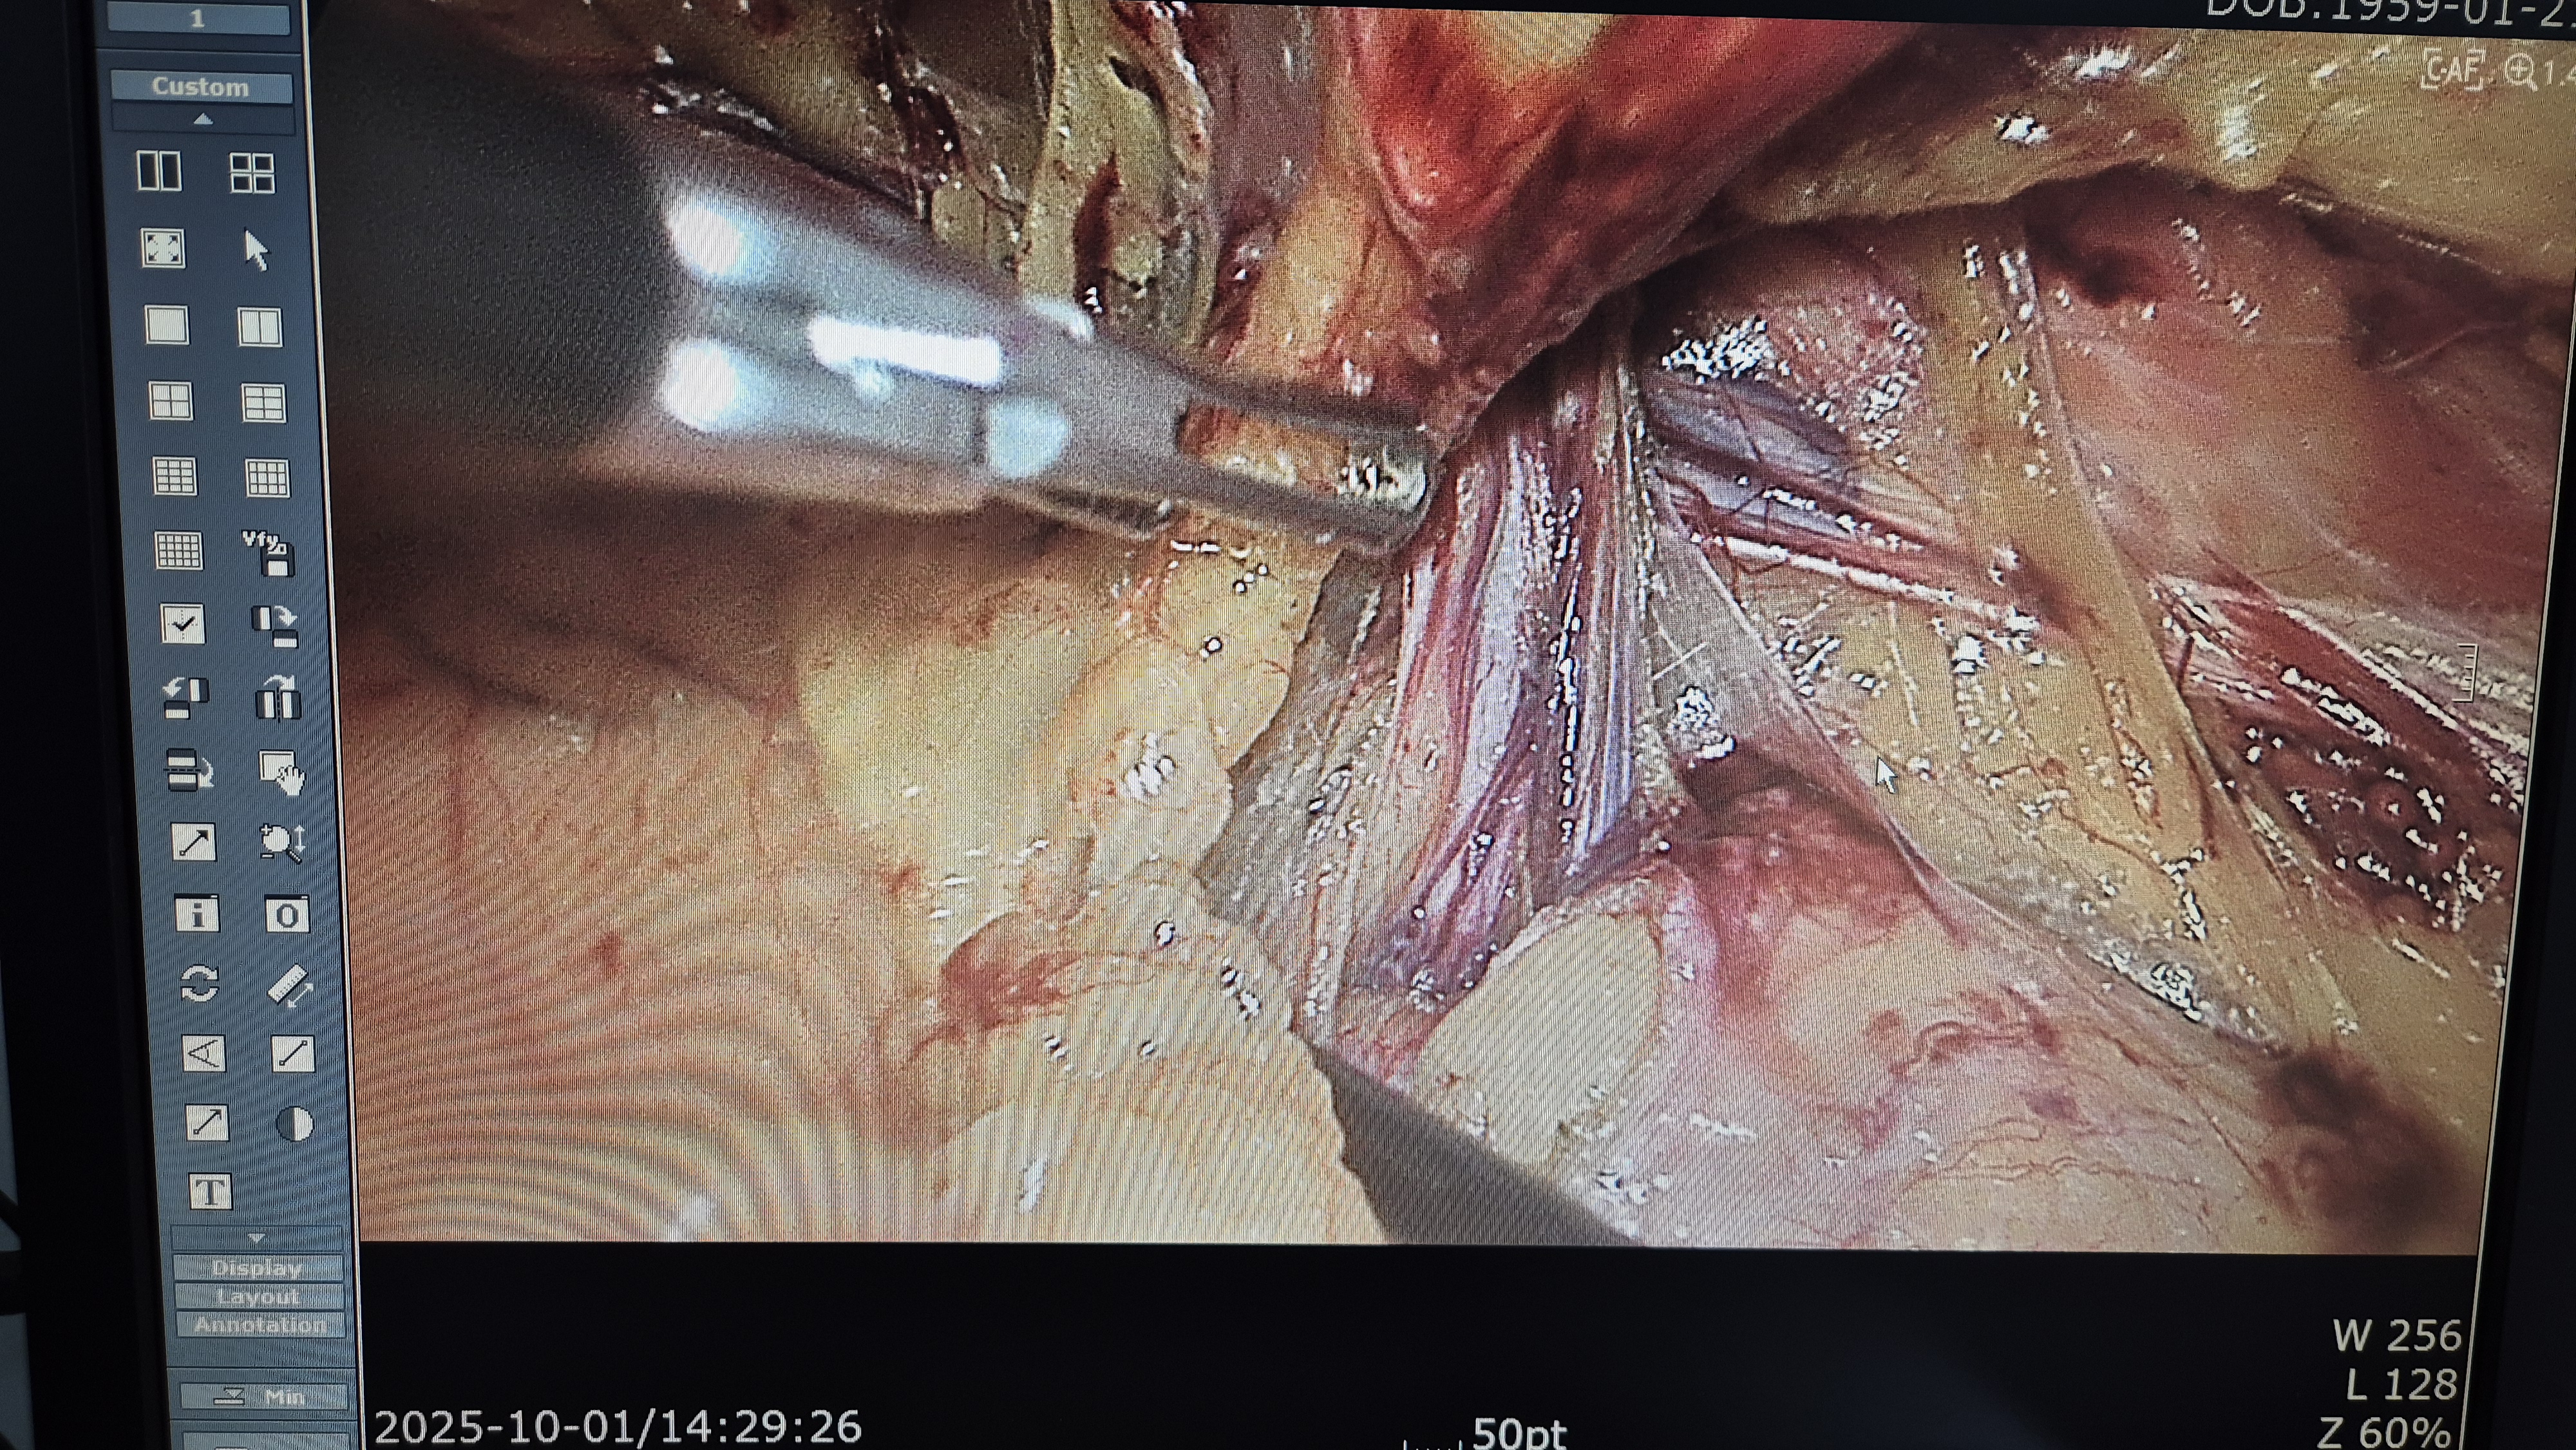

우측 서혜부 종물 주소로 내원하여 초음파 시행후 서혜부 탈장으로 확인되어,

방금 복강경 탈장교정술을 시행했습니다.

탈장 확인후.

박리.

메쉬로 고정.

수술은 15분 걸렸습니다.